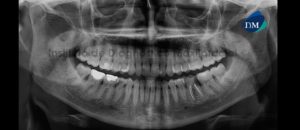

Paciente masculino de 61 años acude al Instituto de Diagnostico Maxilofacial para evaluación general de las piezas dentarias. A la evaluación panorámica se aprecia a